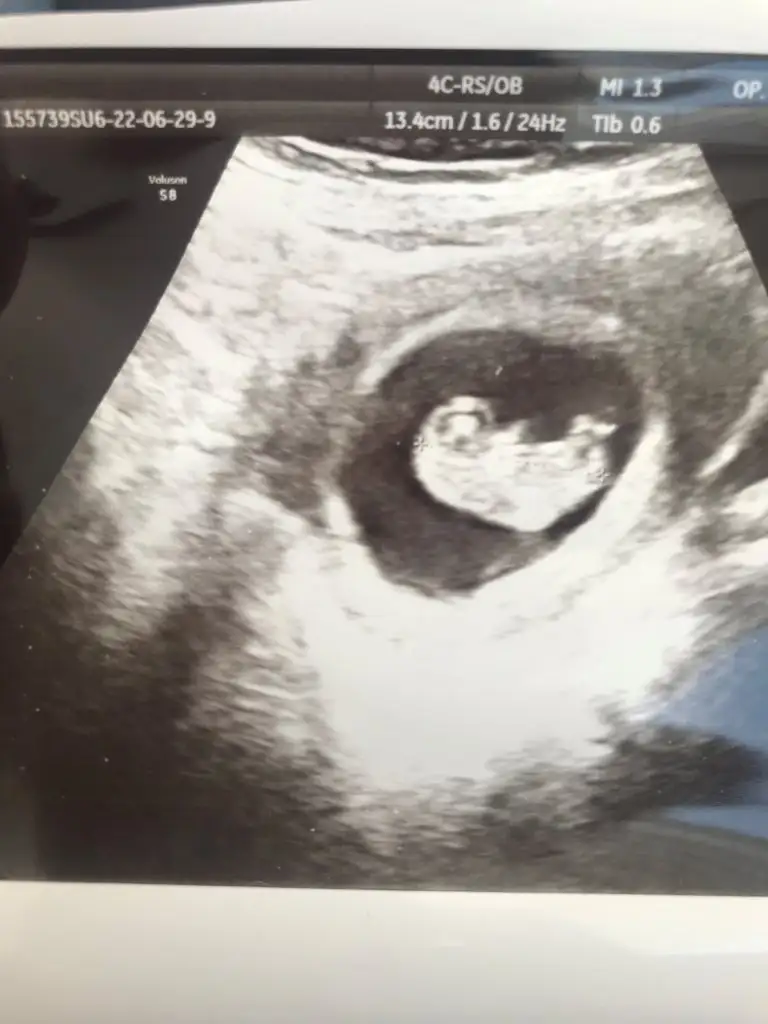

Bana da tahminde bulunursaniz çok sevinirim 😍 bir oğlum var birde kızım olur hayırlısı ve sağlıkla inşallah 🤲🌹

IMG-20220611-WA0004.webp

IMG-20220704-WA0026.webp

Eklentiler

• IMG-20220704-WA0024.webp

IMG-20220704-WA0024.webp

14,8 KB · Görüntüleme: 47